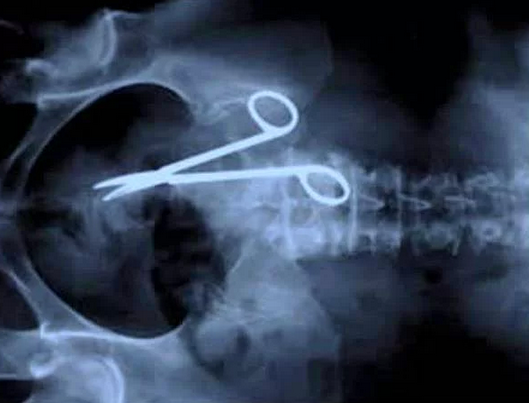

Ameliyatta makas unutma klasiği